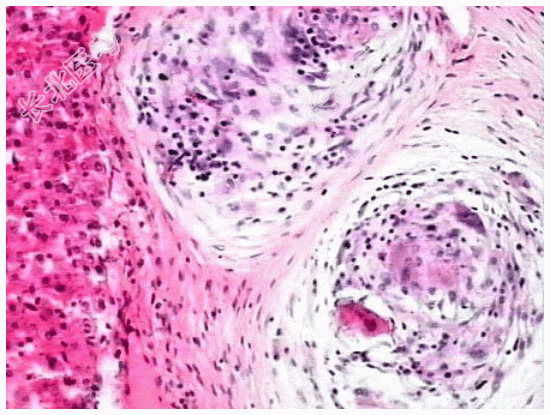

- [材料题] 患者,男,50岁,湖南岳阳人。因贫血、白细胞、血小板减少并腹水入院,临床诊断为“肝硬化”。肝穿刺活检镜下观如图所示,临床拟诊血吸虫性肝硬化。

- 简答题2、该疾病病理学改变表现为?